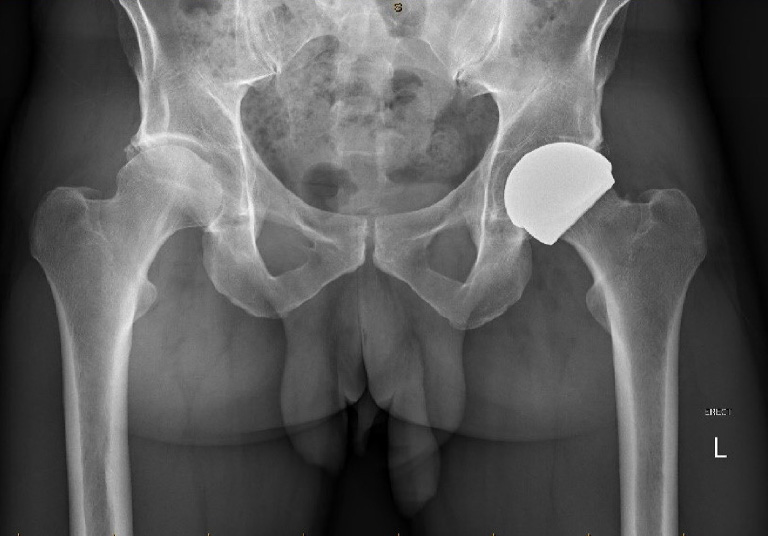

The next generation of hip resurfacings that I use avoids the use of metal bearing surfaces as they are ceramic bearing therefore patients are not exposed to the risks associated with metal wear but still experience the benefits of a hip resurfacing.

- Reduced risk of dislocation - As the femoral head is resurfaced (not replaced) it is the same diameter as the natural femoral head and as such much larger than a conventional hip replacement femoral head. This makes the joint more stable and allows for more vigorous sporting activities that involve repetitive impact loading.

The ReCerf ceramic resurfacing implant received its CE mark for European use in Summer 2025 and the two year clinical results have been published.